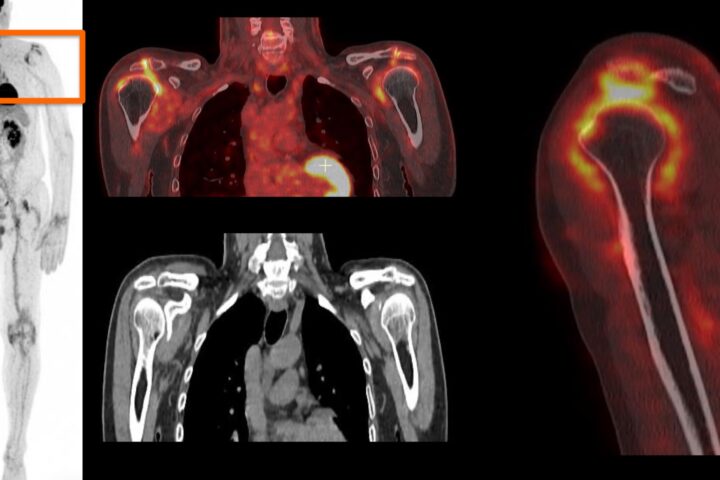

La pseudopolyarthrite rhizomélique (PPR) est une pathologie fréquente, avec une prévalence estimée à 0,7 % et une incidence à 0, 6/100 personnes-année de plus de 50 ans aux États-Unis avec une augmentation d’incidence entre 50 et 80 ans. Le diagnostic se base sur un faisceau d’arguments cliniques, biologiques et d’imagerie. Le diagnostic peut être difficile dans les formes atypiques. La PPR est volontiers associée à une artérite à cellules géantes (ACG) (environ 25 % des cas), et ces 2 affections font partie du même spectre de maladie.